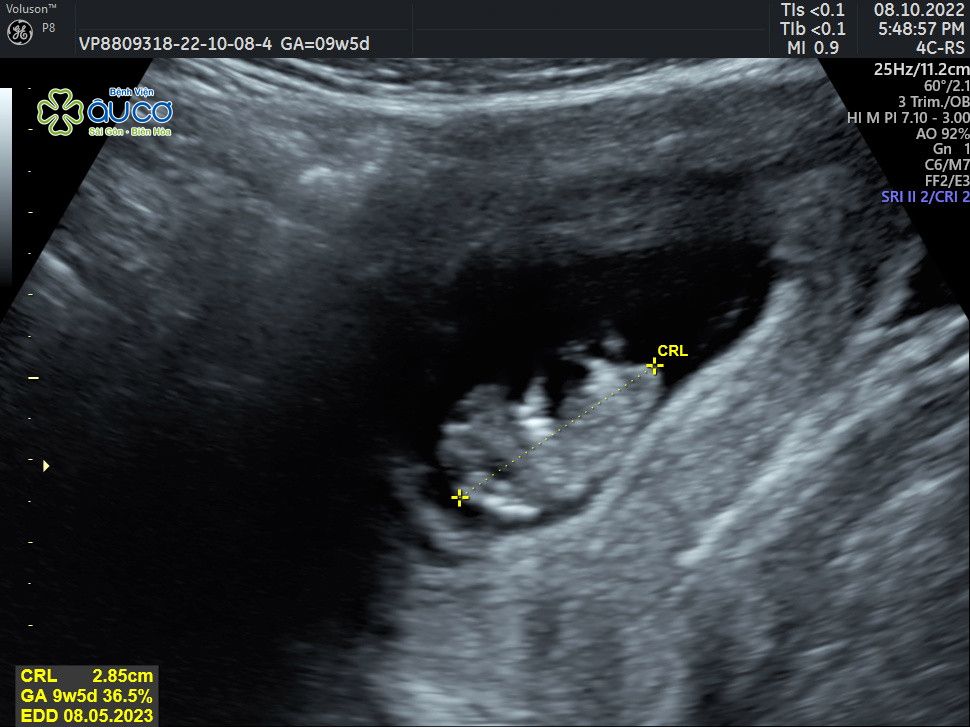

* Những hình ảnh siêu âm đáng yêu nhưng không kém phần nghịch ngợm của con qua các mốc thời gian:

![]() |

| 9 tuần 5 ngày |